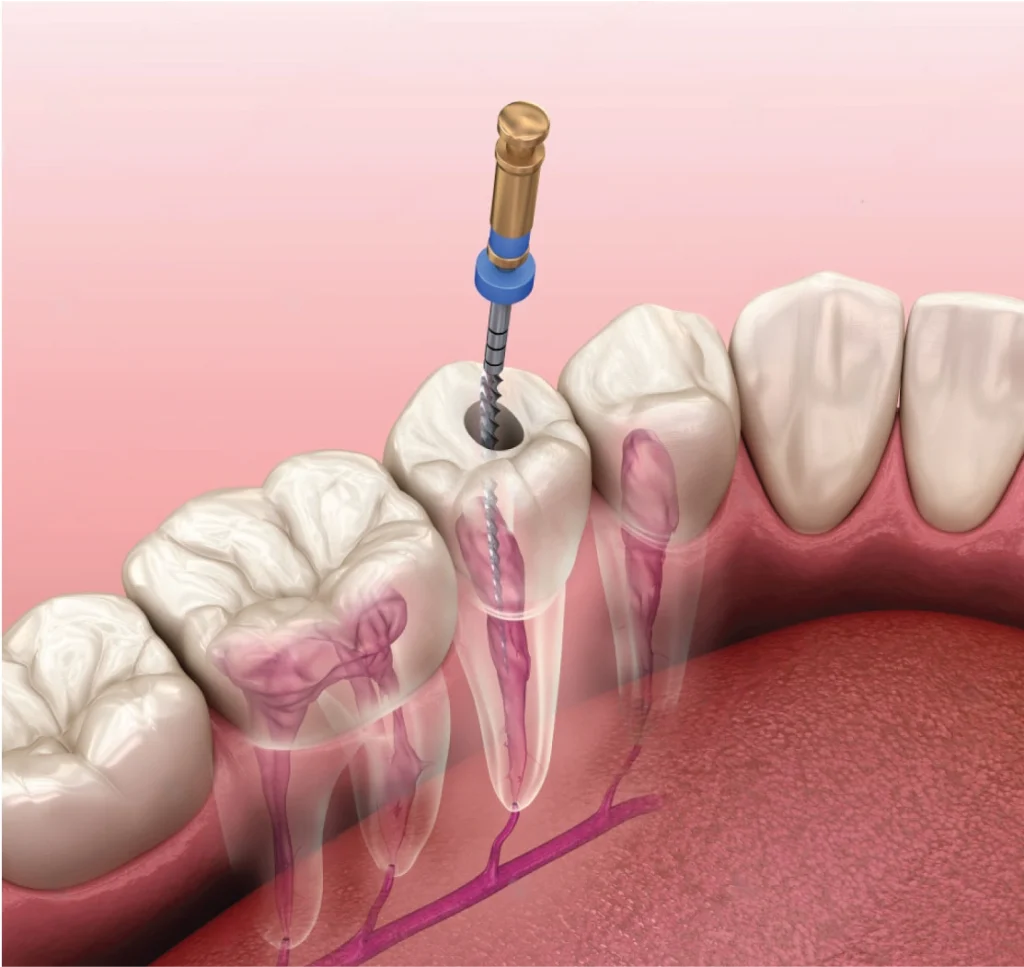

Root canal treatment, also known as endodontic therapy, is a procedure designed to eliminate infection (of the pulp) and save a tooth that has been severely damaged or decayed. Cavities affect the enamel or the surface of the tooth. Underneath them there are soft tissue, nerves, and blood vessels that help the tooth grow and develop.

If that pulp becomes inflamed or infected – due to deep decay, a crack or chip that allowed bacteria to penetrate the tooth, or trauma — the dentist can save the tooth by cleaning and disinfecting it, and then sealing it. In some cases, the tooth will be protected with a dental crown or cap.